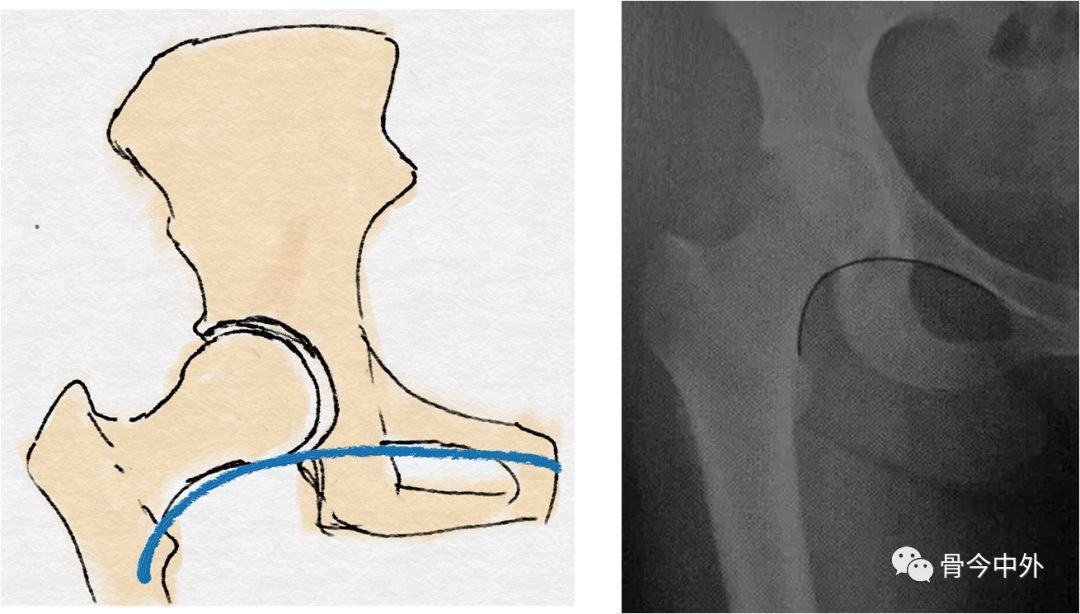

3、骨盆连续性的评估

髂耻线:

连接髂骨内缘与耻骨上缘的弧线

反映髋臼前柱、骨盆前环的完整性

髂坐线:

连接髂骨内缘与坐骨内缘的弧线

反映髋臼内壁、四边体的完整性

泪滴:

U型的弧线

代表了髋臼的内缘

前唇线:

髋臼前缘所连成的弧线(左图中蓝线)

反映髋臼前壁的完整性

后唇线:

髋臼后缘所连成的弧线(左图中红线)

反映髋臼后壁的完整性

8字征:

髋臼前缘与后缘交叉

提示髋臼撞击综合征